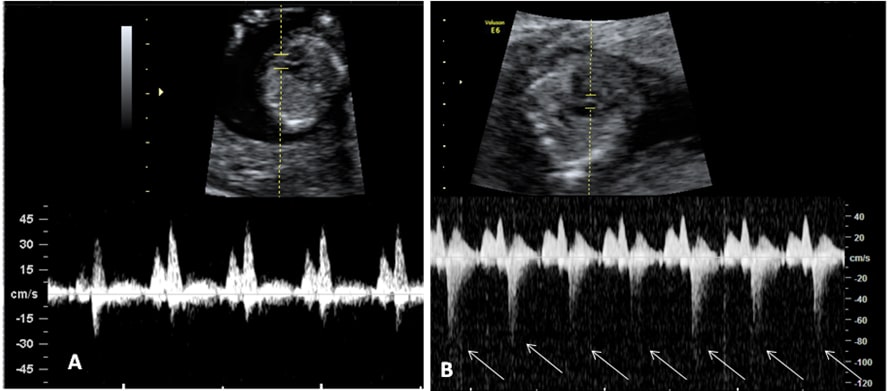

Ecografía del flujo patológico de un feto de la semana 12